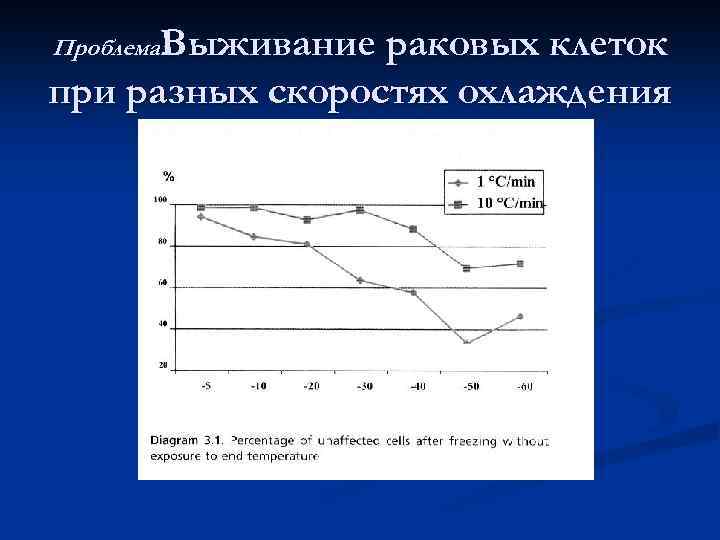

Проблема: Выживание раковых клеток при разных скоростях охлаждения

Проблема: Выживание раковых клеток при разных скоростях охлаждения